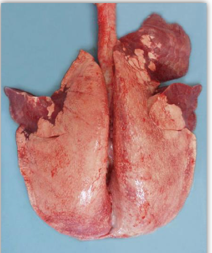

Fibrinous pneumonia

It is cranioventral and may be uni/bilateral